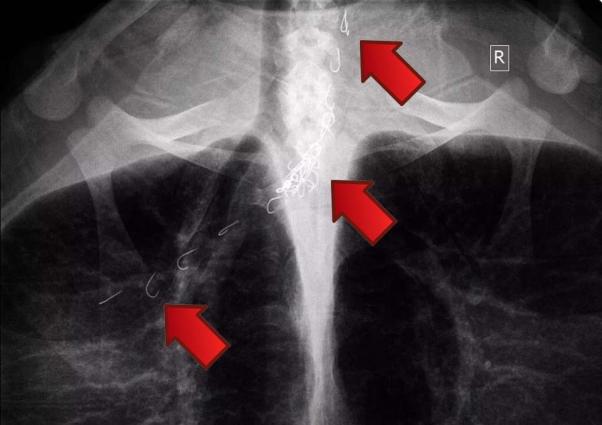

Στην παραλία της Αγίας Άννας στη Νάξο απελευθερώθηκε υγιής σήμερα μετά από 55 μέρες νοσηλείας η θαλάσσια χελώνα, που είχε εντοπιστεί στην περιοχή να έχει καταπιεί αγκίστρια και μεταφέρθηκε για να σωθεί στις εγκαταστάσεις του συλλόγου «ΑΡΧΕΛΩΝ» στις αρχές Οκτωβρίου.

Από το ζώο αφαιρέθηκαν συνολικά 26 που είχαν καρφωθεί στον οισοφάγο του. Οι επιστήμονες άνοιξαν μια τομή στο λαιμό της καρέτα και έβγαλαν με προσοχή την πετονιά και τα αγκίστρια.

Έτσι είδαν την πετονιά να κρέμεται από το στόμα της χελώνας.

Η χελώνα σώθηκε χάρη στην παρατηρητικότητα δύο μελών του συλλόγου «Προστασία Άγριας Ζωής Νάξου» που είδαν τις πετονιές να κρέμονται από το στόμα του ζώου και να είχαν μπλεχτεί στο πτερύγιο της Caretta – caretta και κατάφεραν με κόπο να τη βγάλουν στην στεριά και να τη στείλουν στη συνέχεια για περίθαλψη.

Η ακτινογραφία έδειξε τι είχε καταπιεί και πόσο βαθιά είχαν φτάσει τα αγκίστρια.